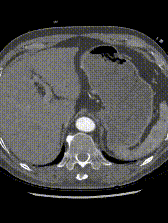

案例一(巨大成角瘤颈):患者瘤颈虽长但呈90度成角。在完成髂动脉重建后,采用Reverse技术释放主体支架。术中造影显示,支架完美贴合扭曲的血管大弯侧,术后一月复查CTA,原有的少量内漏已完全消失。

案例二(短瘤颈+梯形瘤颈):患者近端瘤颈长度不足1cm,且伴有大量附壁血栓。选用适当oversize的支架,结合Reverse技术释放,支架主体自动“寻找”并适应最佳的贴附区域,最终造影显示无明确内漏。

案例三(梯形瘤颈):3年前肾结石,在治疗复查过程中发现腹主动脉瘤。

案例四(梯形瘤颈):因下肢髋部疼痛行腰椎检查时发现腹主动脉瘤,进一步CTA认证确诊为腹主动脉瘤。

案例五:查体发现腹主动脉,行CTA确认腹主动脉瘤伴血栓形成。

截至目前,采用Reverse技术处理不良瘤颈的初步经验(21例)显示,术中发生明显I型内漏仅3例,其中2例经弹簧圈栓塞处理,1例在随访中自行消失。这表明Reverse技术在处理不良瘤颈时,是一种安全、有效且能显著减少内漏发生的手段。